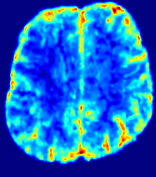

TimeSlice(i)(ii)(iii)(iv)(v)(vi)Refer to caption00777141414212121282828353535Refer to caption(a)(b)Refer to captionRefer to captionRefer to captionRefer to captionRefer to captionRefer to captionRefer to captionRefer to captionRefer to captionRefer to captionRefer to captionRefer to captionRefer to captionRefer to captionRefer to captionRefer to captionRefer to captionRefer to caption(a)(b)Refer to captionRefer to captionRefer to captionRefer to captionRefer to captionRefer to captionRefer to captionRefer to captionRefer to captionRefer to captionRefer to captionRefer to captionRefer to captionRefer to captionRefer to captionRefer to captionRefer to captionRefer to caption(a)(b)Refer to captionRefer to captionRefer to captionRefer to captionRefer to captionRefer to captionRefer to captionRefer to captionRefer to captionRefer to captionRefer to captionRefer to captionRefer to captionRefer to captionRefer to captionRefer to captionRefer to captionRefer to caption(a)(b)Refer to captionRefer to captionRefer to captionRefer to captionRefer to captionRefer to captionRefer to captionRefer to captionRefer to captionRefer to captionRefer to captionRefer to captionRefer to captionRefer to captionRefer to captionRefer to captionRefer to captionRefer to caption(a)(b)Refer to captionRefer to captionRefer to captionRefer to captionRefer to captionRefer to captionRefer to captionRefer to captionRefer to captionRefer to captionRefer to captionRefer to captionRefer to captionRefer to captionRefer to captionRefer to captionRefer to captionRefer to caption(a)(b)Refer to captionRefer to captionRefer to captionRefer to captionRefer to captionRefer to captionRefer to captionRefer to captionRefer to captionRefer to captionRefer to captionRefer to captionRefer to captionRefer to captionRefer to captionRefer to captionRefer to captionRefer to caption

Figure 5: Predicted concentration time series for the same patient shown in Fig. 3, where (i)-(vi) correspond to slices #1-6 respectively. Each grouped row displays (a) the measured concentration image sequences and (b) the predicted concentrations at corresponding time points.

3.2 Predicted CA Concentration

To better illustrate the prediction accuracy, and therefore the estimation accuracy of 𝐕𝐕{\bf V} and D𝐷{D}, of PIANO, we provide the corresponding predicted time-series of CA concentration images in Fig. 5 and Fig. 6 for the same patients in Fig. 3 and Fig. 4, respectively. We see that PIANO is capable of predicting the CA concentration given their initial state, indicating its ability to successfully capture 𝐕𝐕{\bf V} and D𝐷{D}. Note that although the concentration values for these two patients differ considerably, caused by the different total volume of injected CA, PIANO is still able to provide plausible estimates.